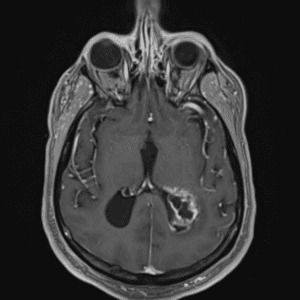

Case #14

CNS toxoplasmosis